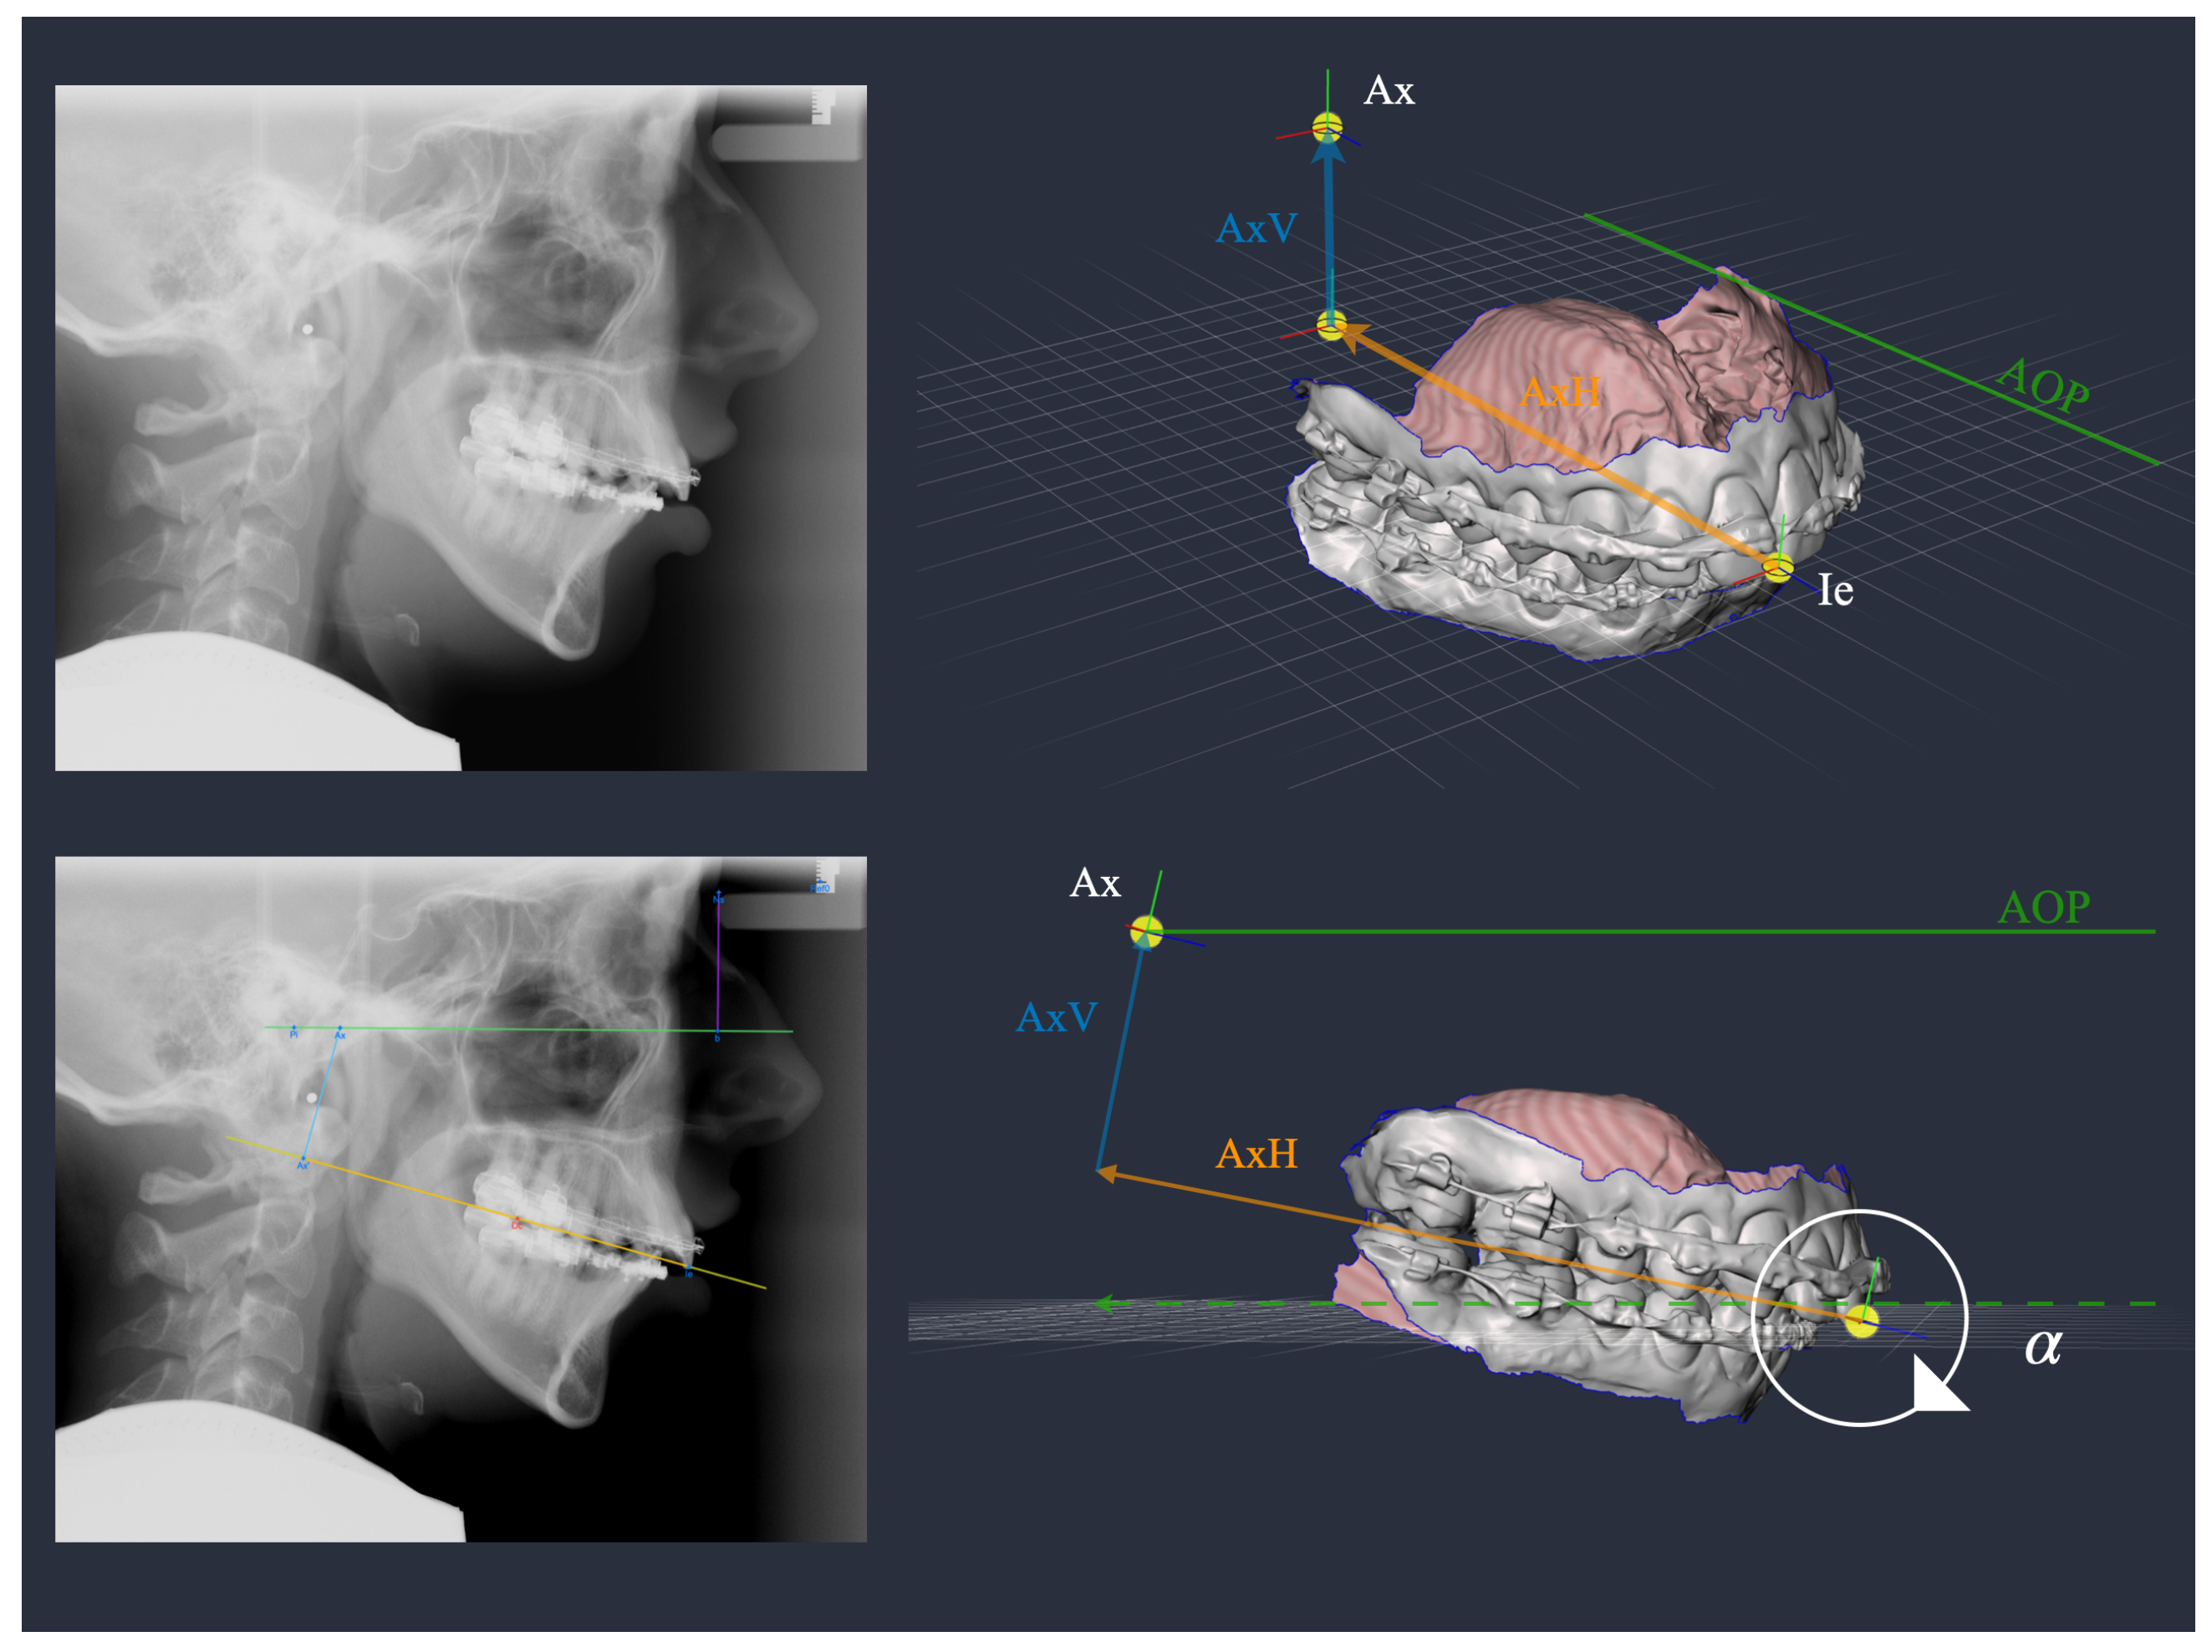

2. Materials and Methods

| 323 | 7.6 | 5.3 | 191 | 6.5 | 5.0 | ||

| AxV | 323 | 30.2 | 5.7 | 191 | 35.8 | 5.7 | <0.001 |

| AxH | 323 | 88.0 | 6.7 | 191 | 93.1 | 8.1 | <0.001 |

| AxV | 128 | 36.2 | 4.6 | 204 | 26.5 | 3.8 | 182 | 35.9 | 4.5 | <0.001 1 | |

| AxH | 128 | 98.9 | 5.5 | 204 | 88.1 | 5.4 | 182 | 85.6 | 5.6 | <0.001 | |